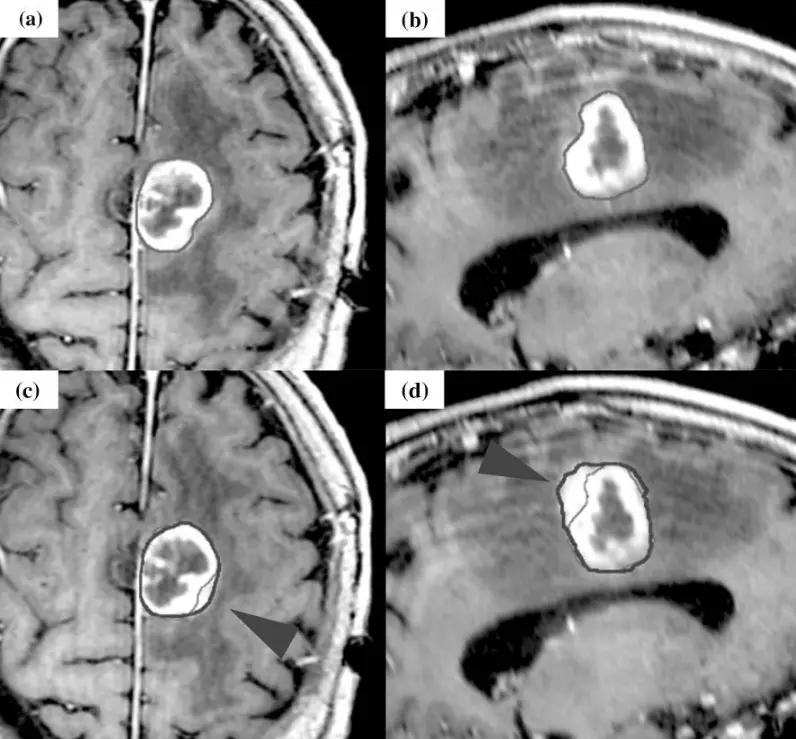

Ring-enhancing lesion: A ring-enhancing lesion appears as a bright rim surrounding a darker centre after contrast dye is administered during an MRI or CT scan18. The ring is due to contrast uptake at the edge of the lesion, often raising concern for aggressive or infectious processes.

Dural tail: This is a tapered enhancement on the brain lining, which is typical of meningioma, seen in 60-72 per cent of cases22.

30. Wang M, Wang Z, Ren P, et al. Meningioma with ring enhancement on MRI: a rare case report. BMC Med Imaging. 2021;21:22. doi:10.1186/s12880-021-00555-x